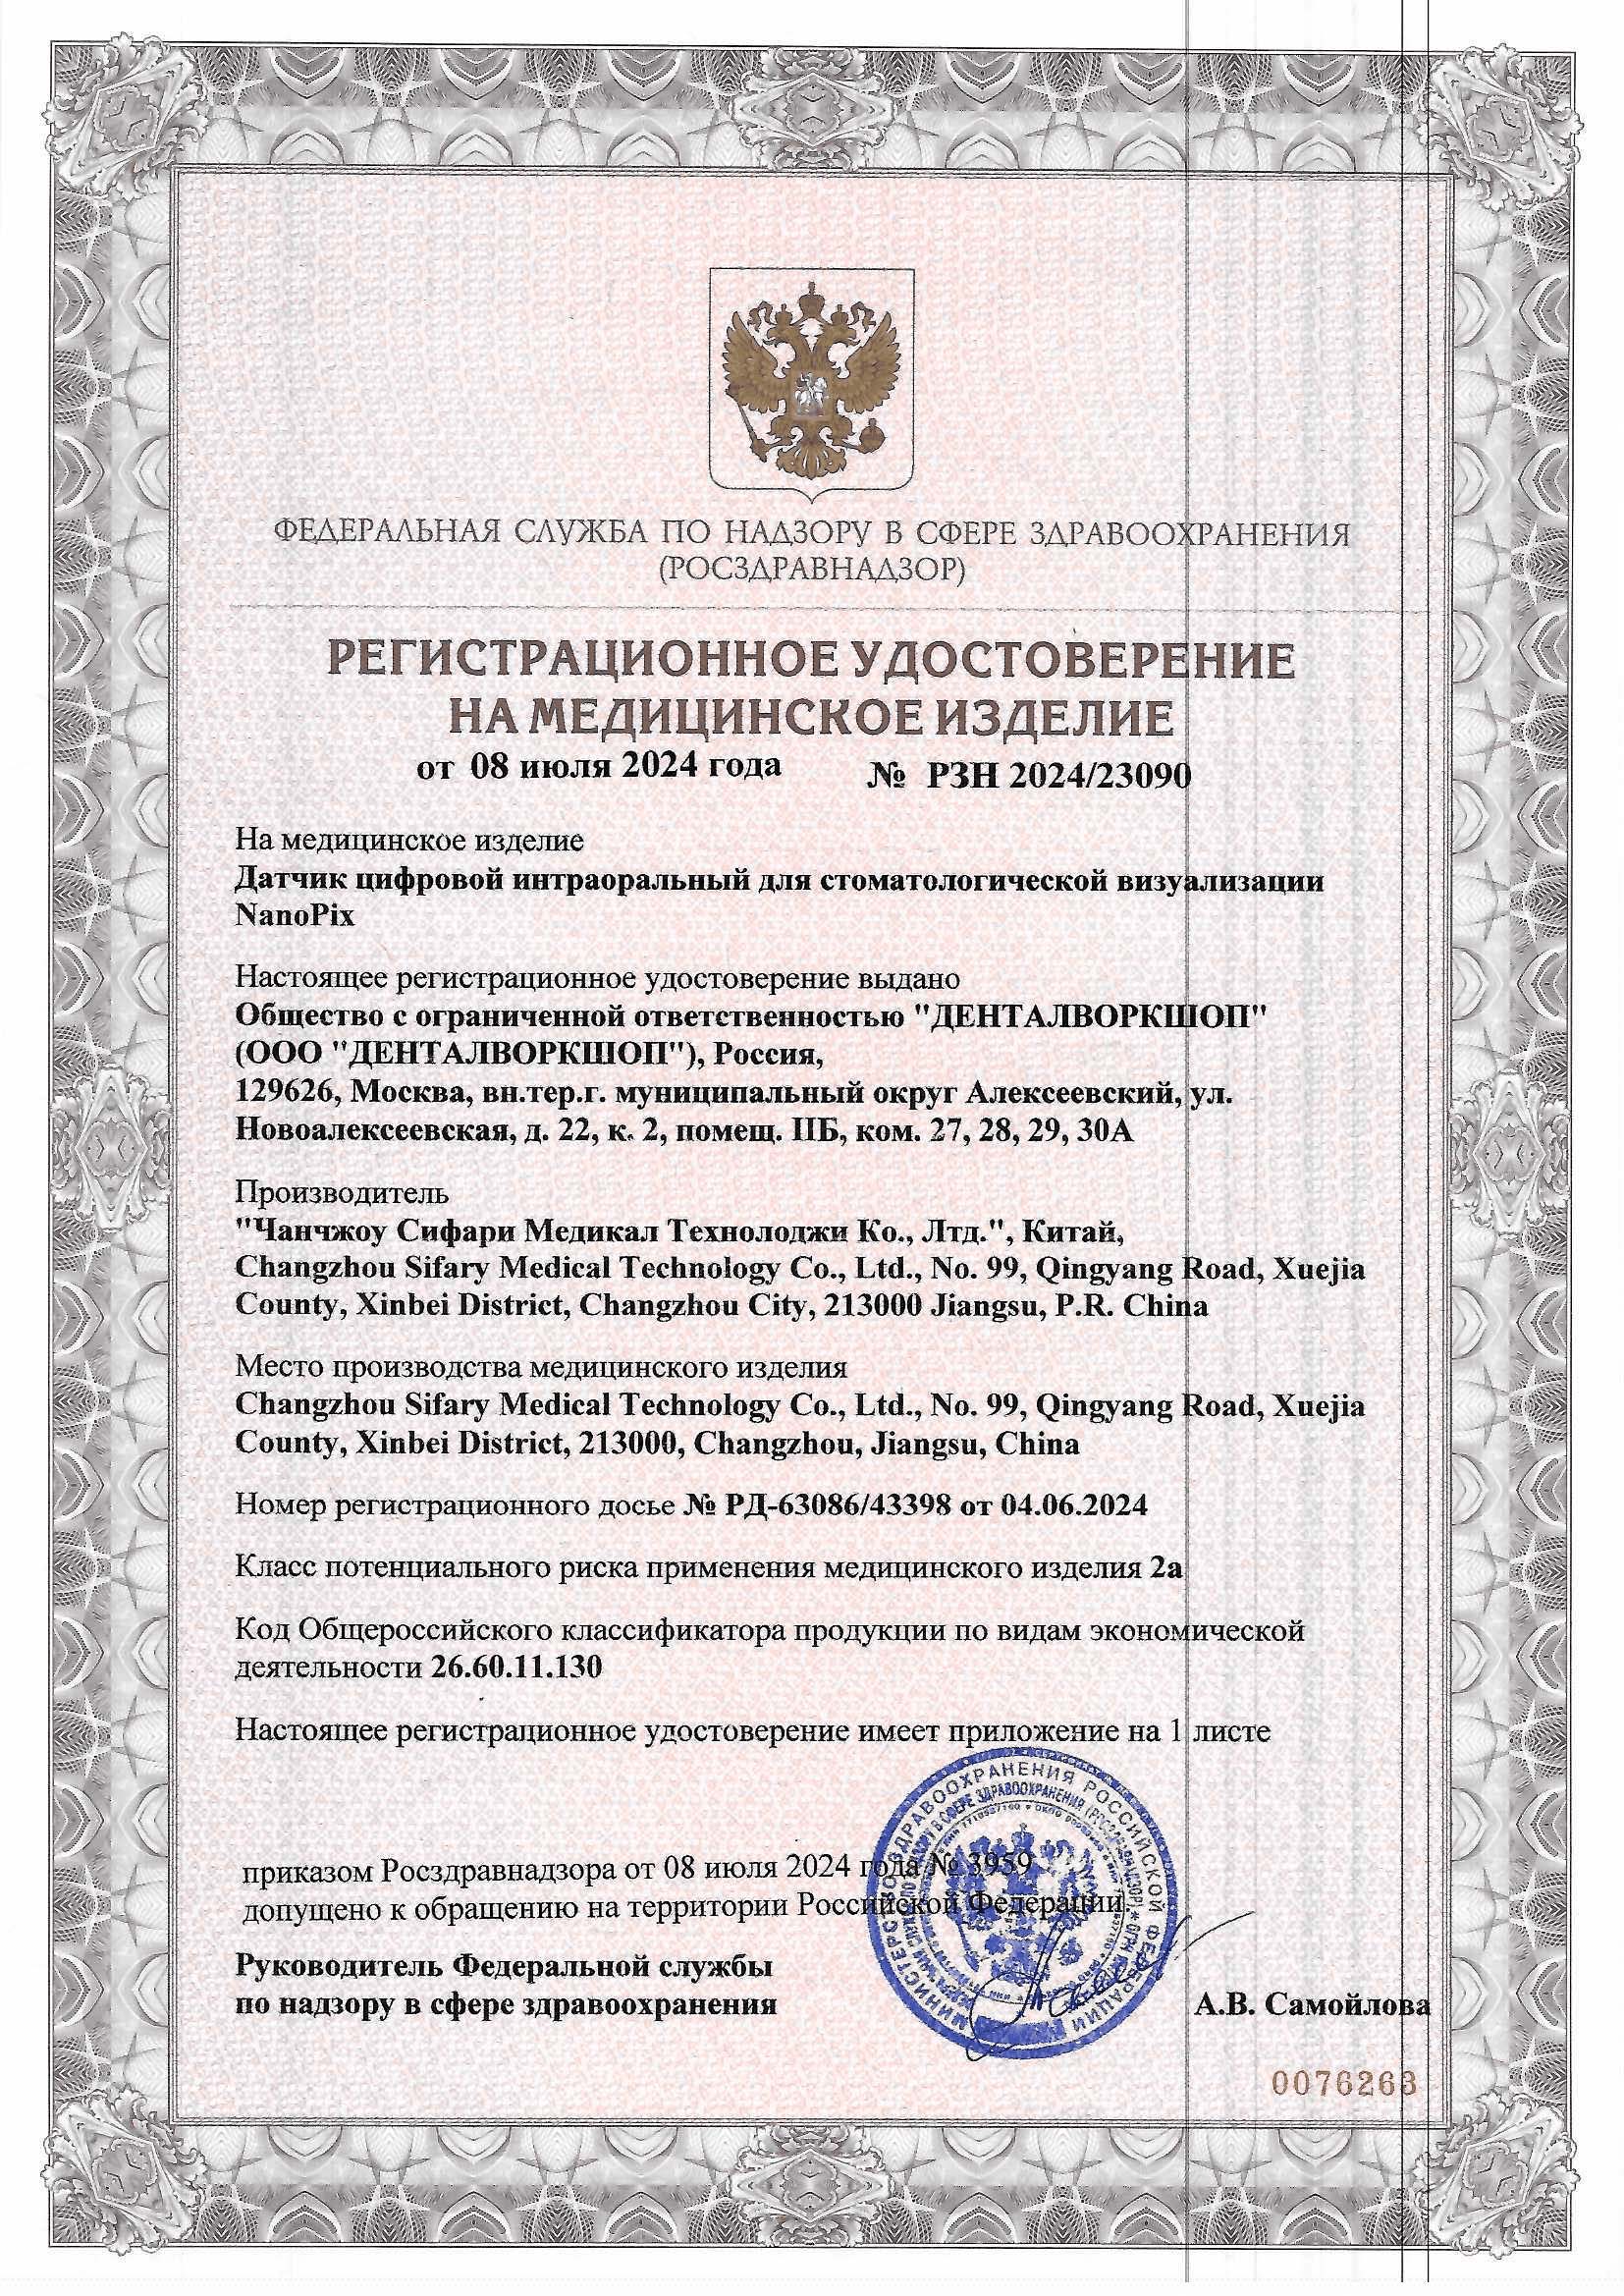

Визиограф NANOPIX с искусственным интеллектом (Nano AI)

Визиограф NANOPIX с искусственным интеллектом (Nano AI)

129000 ₽ 159000 ₽

Автоматическое определение экспозиции. Супертонкий датчик - 4,5 мм. Технология APS CMOS. Более 5000 снимков без потери качества. Разрешение - 25 пар линий/мм.

Гарантия 1 год

Визиограф NANOPIX с искусственным интеллектом (Nano AI)

Автоматическое определение экспозиции. Супертонкий датчик - 4,5 мм. Технология APS CMOS. Более 5000 снимков без потери качества. Разрешение - 25 пар линий/мм.